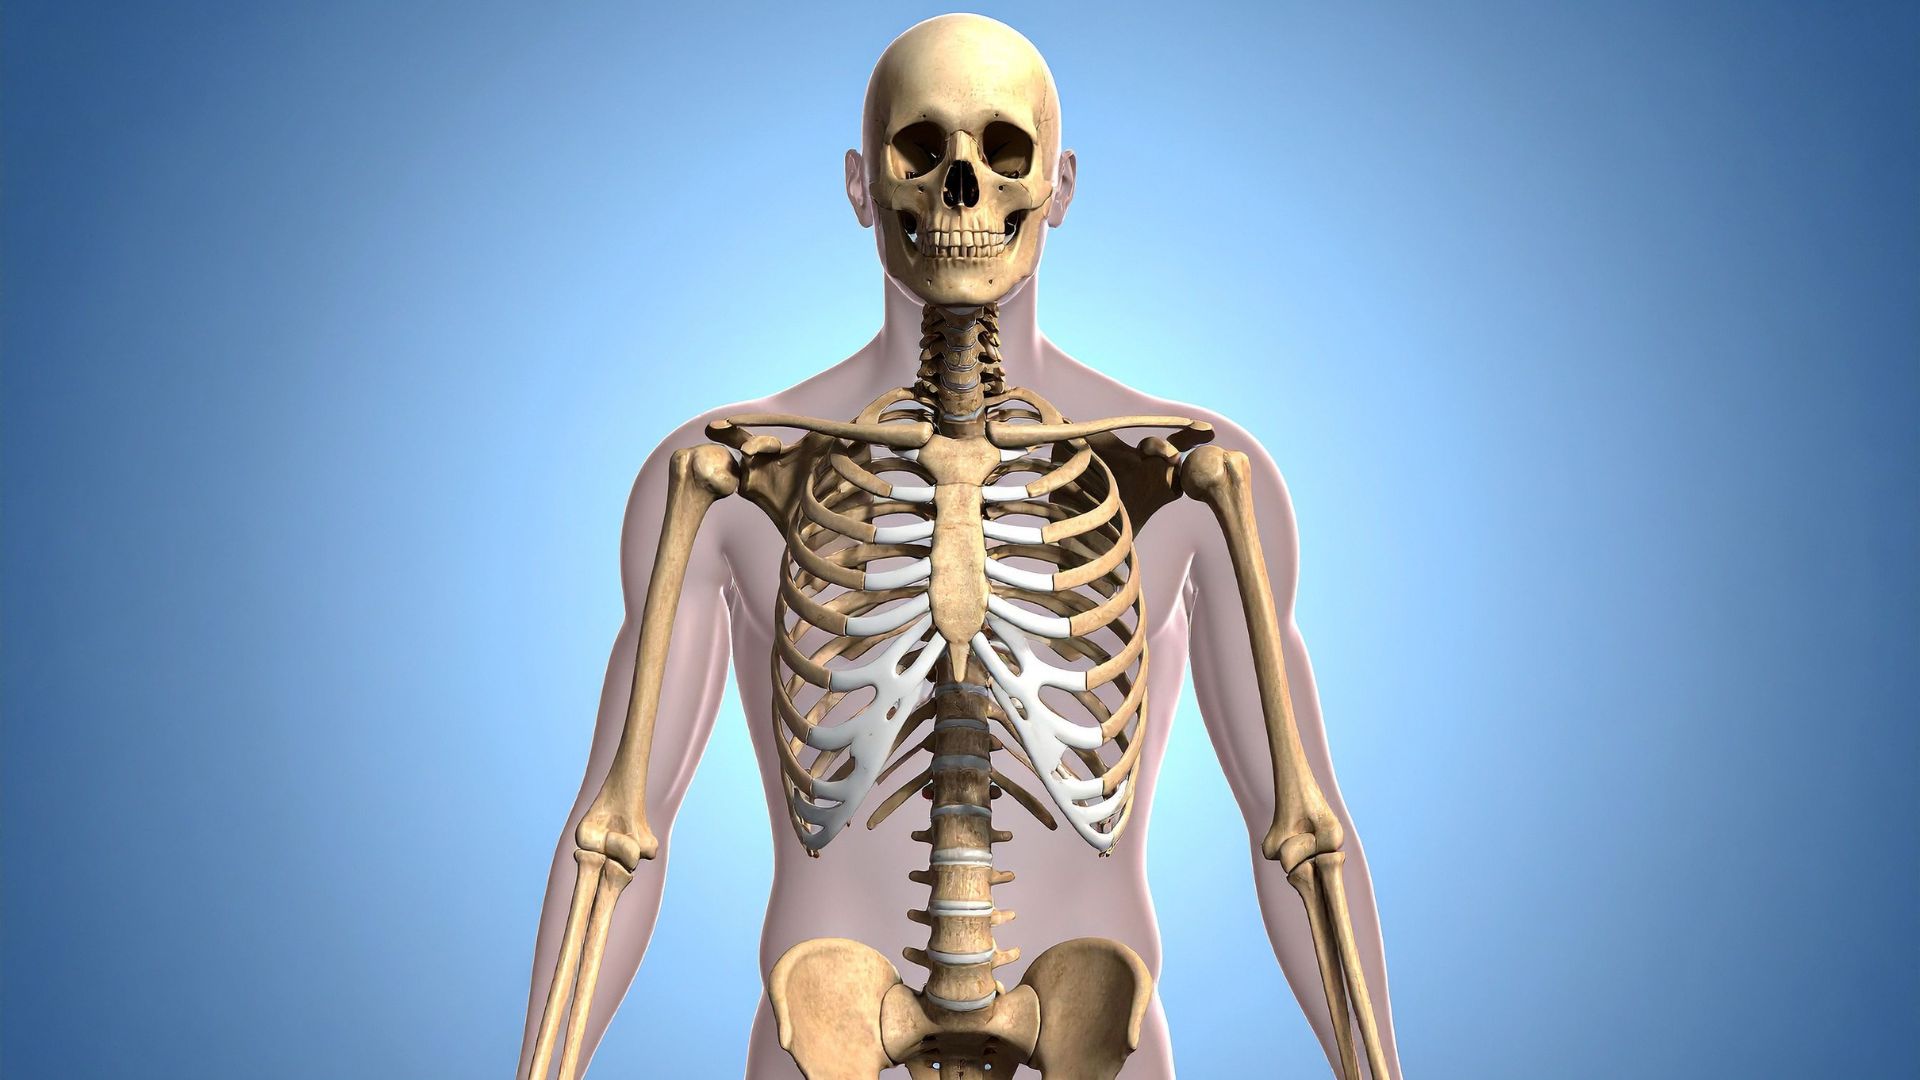

Xương sườn là một phần cấu trúc quan trọng của hệ xương trục, tạo nên lồng ngực cùng với xương ức và cột sống ngực. Chúng có hình cong dài, hơi dẹt, uốn cong từ phía sau ra trước, giúp bảo vệ các cơ quan nội tạng quan trọng như tim, phổi và các mạch máu lớn trong lồng ngực. Ngoài chức năng bảo vệ, xương sườn còn đóng vai trò quan trọng trong quá trình hô hấp, khi phối hợp cùng cơ hoành và cơ liên sườn để làm giãn và co lồng ngực, giúp không khí lưu thông ra vào phổi.

Xương sườn là cấu trúc quan trọng của hệ xương trục, giúp bảo vệ các cơ quan nội tạng quan trọng

Một người trưởng thành bình thường có tổng cộng 24 xương sườn, chia thành 12 đôi đối xứng hai bên lồng ngực. Cấu trúc này gồm 7 đôi xương sườn thật đầu tiên, có liên kết trực tiếp với xương ức qua sụn sườn riêng biệt. Tiếp theo là 3 đôi xương sườn giả, kết nối gián tiếp với xương ức thông qua sụn của các xương sườn phía trên. Cuối cùng là 2 đôi xương sườn cụt, không có sự gắn kết với xương ức mà chỉ bám vào cột sống. Một số ít trường hợp có thể xuất hiện thêm xương sườn cổ - một dị dạng bẩm sinh hiếm gặp.

Xương sườn là những xương dài, cong và dẹt, giữ vai trò quan trọng trong việc tạo nên khung lồng ngực, góp phần bảo vệ nội tạng và hỗ trợ hô hấp. Về mặt giải phẫu, mỗi xương sườn được chia thành ba phần chính, với đặc điểm cấu tạo như sau:

• Đầu xương: Là phần gần với cột sống, có hai diện khớp, cho phép kết nối với thân của hai đốt sống ngực liền kề, giúp tạo sự ổn định cho lồng ngực.

• Cổ xương: Là đoạn ngắn nối giữa đầu xương và phần thân. Cổ xương là nơi bám của dây chằng, đồng thời thường có rãnh nhỏ để các mạch máu và dây thần kinh liên sườn đi qua.

• Thân xương: Là phần dài nhất, có dạng cong hình cánh cung, bề mặt ngoài lồi, bề mặt trong lõm và chứa rãnh sườn chạy dọc theo bờ dưới để bảo vệ mạch thần kinh liên sườn.

Ở phía trước, các xương sườn thật nối trực tiếp với xương ức qua sụn sườn, xương sườn giả nối gián tiếp, còn xương sườn cụt (số 11 và số 12) không có đầu nối phía trước. Cấu tạo này đảm bảo độ linh hoạt cần thiết cho chức năng hô hấp và bảo vệ các cơ quan trong lồng ngực.